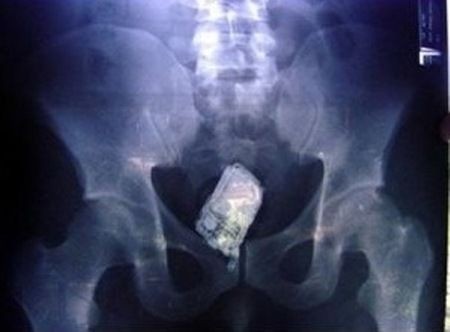

1. Een mobieltje die nog een paar keer afging ook

Een advocaat had een mobieltje mee onder de douche genomen, het gleed uit zijn handen, de advocaat gleed zelf ook uit en hoppa, het mobieltje zat vast in de kont. Tijdens het verwijderen ging de mobiele telefoon nog drie keer af ook.